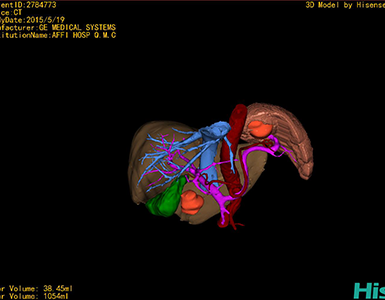

将0.625mm双源薄层CT资料的静脉期和动脉期Dicom格式文件导入海信CAS系统。

通过调节窗宽窗位调整CT序号,对肿瘤,肝实质,胆囊,下腔静脉,肿瘤,肝动脉、门静脉及肝静脉等进行三维重建;系统自动计算肿瘤体积和肝脏体积。

模拟手术操作,自动计算切除肿瘤体积。肝脏体积为1054ml,肿瘤体积为38.45ml,肿瘤体积为肝脏体积的3.6%,通过比对50-60岁正常肝脏体积为1330.41±329.13 ml,通过术前模拟手术,精准判断切除后剩余肝脏体积能耐受,避免肝衰竭发生。

术前三维重建:

重建图片